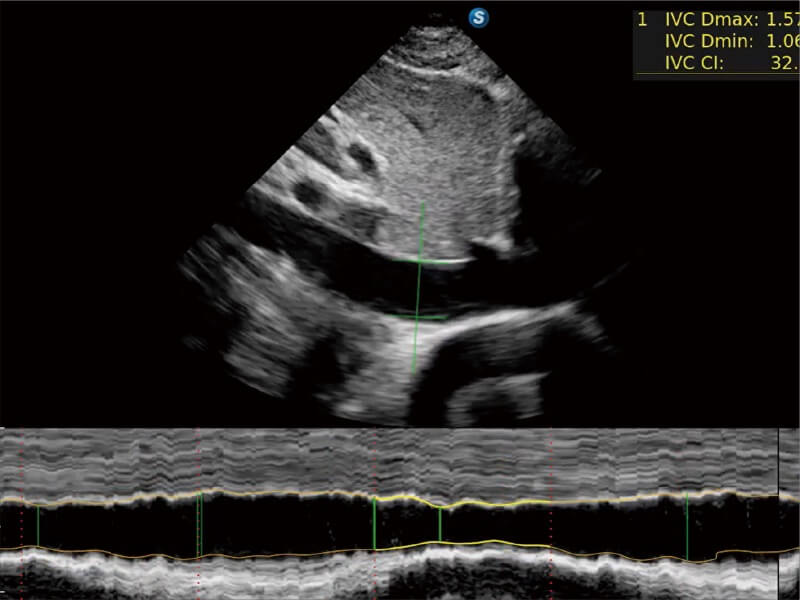

E11搭载了丰富的自动化测量工具,以及专为POC科室定制的高级功能;同时配备了为急诊医师量身打造的 SonoFast急重症超声流程,以帮助临床医生最大限度的提升工作效率

将测量、体标和注释等关键内容整合到一个页面中。精简界面,诊断更有针对性。

可助力简化工作流程,同时提升操作标准化程度,并减少按键次数,缩短检查时间。